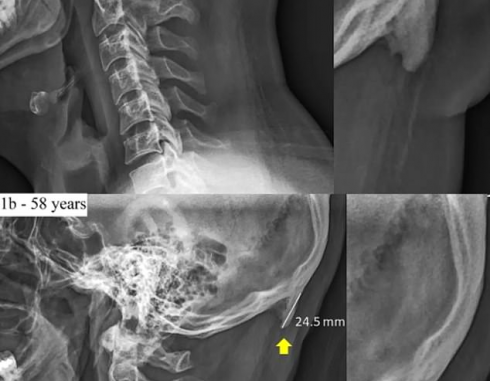

Le persone passano così tanto tempo a guardare lo smartphone e il tablet che “punte” ossute stanno crescendo sul retro delle loro teste, rivelano gli scienziati. I ricercatori hanno riferito che un numero crescente di persone ha uno sviluppo chiamato protuberanze occipitali esterne allargate alla base del cranio. Considerati rari quando furono discussi per la prima volta nel 1800, ora possiamo essere in grado di sentire le ossa ossute con le dita o vederle su persone calve. E i più giovani li stanno sviluppando più velocemente, con la ricerca che mostra spaventose punte che sono più comuni tra i 18 e i 30 anni. Gli scienziati dell’Università della Sunshine Coast nel Queensland, in Australia, hanno svolto ricerche dettagliate sul fenomeno. Hanno scansionato più di mille teschi appartenenti a persone di età compresa tra i 18 e gli 86 anni, secondo i report della BBC Future. Il dott. David Shahar, ricercatore principale, ha dichiarato alla BBC: “Sono stato un clinico per 20 anni e solo nell’ultimo decennio ho scoperto sempre più che i miei pazienti hanno questa crescita sul cranio”. Il dott. Shahar suggerisce che la ragione per cui il picco osseo sta diventando più comune è la quantità di tempo in cui le persone – in particolare i giovani – passano a guardare in basso. Le ore trascorse a scorrere su smartphone, tablet e laptop potrebbero mettere a dura prova le parti del corpo meno utilizzate che cambiano effettivamente le parti del corpo. In particolare, i muscoli che collegano il collo alla parte posteriore della testa sono sotto sforzo mentre cercano di tenere fermo il cranio – una testa media per adulti può pesare circa 5 kg. In risposta a quei muscoli che diventano sempre più forti, suggerisce il dott. Shahar, lo scheletro sviluppa nuovi strati ossei per rinforzare e allargare l’area. La ragione di ciò, suggeriscono, è una “rivoluzione tecnologica manuale”. Secondo una ricerca rivelata lo scorso anno, la persona media nel Regno Unito ha speso 24 ore a settimana – circa tre e mezza al giorno – sui propri smartphone nel 2017. In media, le persone controllano i loro telefoni ogni 12 minuti, secondo le statistiche della Ofcom, ‘autorità competente e regolatrice indipendente per le società di comunicazione nel Regno Unito. Circa il 78% dei cittadini britannici possiede uno smartphone e un adulto su cinque trascorre 40 ore o più online ogni settimana. Il dott. Shahar e colleghi hanno scritto nel loro studio che “il carico meccanico ripetuto e sostenuto” porta all’adattamento dei tendini e dei tessuti connettivi. Hanno detto: “Lo sviluppo di EOP ampliato può essere attribuito a, e spiegato da, l’uso estensivo di attività basate sullo schermo da parte di individui di tutte le età, compresi i bambini, e la cattiva postura associata. “Disturbi muscoloscheletrici legati a posture scorrette durante l’utilizzo di computer e tablet sono stati ampiamente studiati e sono stati identificati come un fattore di rischio per lo sviluppo di sintomi correlati a collo, spalle e avambracci.” E il dott. Shahar ha detto che, anche se è improbabile che i noduli ossei possano causare effetti dannosi, potrebbero non andare mai via. Ha aggiunto: “Immagina di avere stalattiti e stalagmiti, se nessuno li disturba, continueranno a crescere”.